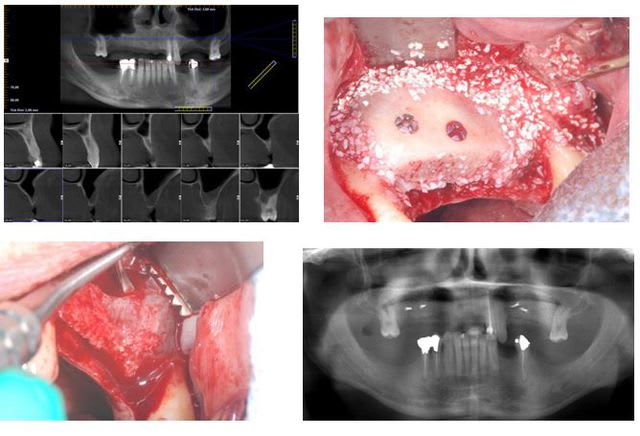

ce matin implantation à 5 mois post sinus lift + greffe onlay Biobank. Très bonne stabilité primaire.

Planche 1 fx9sim - Eugenol

Planche 2 k3neab - Eugenol

la résorption était majoritairement vestibulaire

les forages ont été effectués volontairement dans le couloir prothétique ce qui les a situé pratiquement à la jonction entre la crête résiduelle et le greffon et cela laisse ici justement une bonne épaisseur de matériau greffé en vestibulaire en prévision d'une éventuelle future résorption.

après voilà, nous verrons si la résorption sera GARANTIE, garantie ou absente.